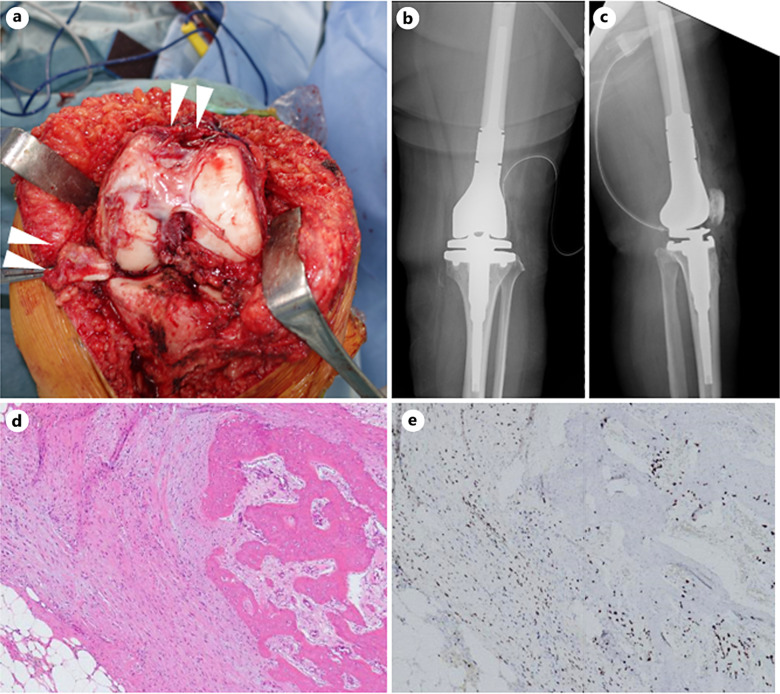

Case presentation: A 45-year-old woman with a pathological fracture of the left distal femur was diagnosed with GCTB based on the biopsy findings, which revealed both H3.3 G34W and nuclear β-catenin positivity. Eight courses of neoadjuvant denosumab therapy were administered to visualize the extraskeletal lesions; subsequently, en bloc resection with megaprosthetic reconstruction was successfully performed. Pathological examination revealed intratumoral ossification without osteoclastic giant cells. Two years after the surgery, no evidence of local recurrence was recorded.

Conclusion: Neoadjuvant denosumab therapy is an effective approach for managing β-catenin positive GCTB with pathological fractures as it promotes intratumoral ossification and facilitates complete resection of GCTB, including extraskeletal lesions.